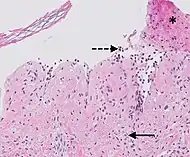

| Prevesicular stage of bullous pemphigoid | Image at right shows influx of inflammatory cells including eosinophils and neutrophils in the dermis (solid arrow) and blister cavity (dashed arrows), and deposition of fibrin (asterisks).[19] However, the diagnosis of bullous pemphigoid consist of at least 2 positive results out of 3 criteria:[20]

|

![]() |